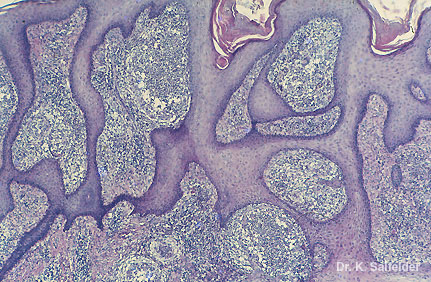

Abb. 7,35: Chromoblastomykose

Typische chronische Entzuendung der Haut. Pilzzellen sind bei dieser Vergroesserung nicht zu sehen. HE-Faerbung